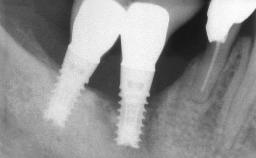

Biological complications caused by undetected cement residue have been receiving much attention. Excess cement might be responsible not only for rapidly developing of peri-implantitis, but also for delayed or chronic manifestations of the disease many years after cementation (Wilson 2009; Linkevicius and coworkers 2013). Invitro and clinical studies have shown that it is very difficult or even impossible to completely clean up excess cement at subgingival margins, so popular in cemented restorations (Agar and coworkers 1997; Linkevicius and coworkers 2011, 2012). Possible outcomes of biological complications due to excess cement range from temporary inflammation of the peri-implant soft tissues without any serious esthetic and functional consequences all the way to implant loss. This report describes a case of peri-implantitis caused by residual cement; as well as the management and quite unusual resolution of the complication. The patient presented in 2009 with a draining sinus tract, tenderness on chewing, and tissue contact above the implant-supported restoration. The implant had been restored approximately three years before.

Case Type Single-Tooth Space

# of Teeth 1

# of Implants 1

Type of Implants Two-Piece